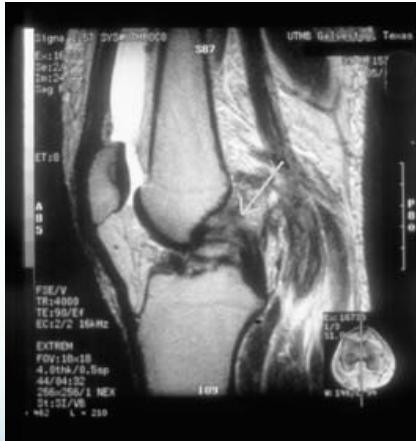

Diagnostic Investigations

MRI

- Best imaging modality for PCL injuries